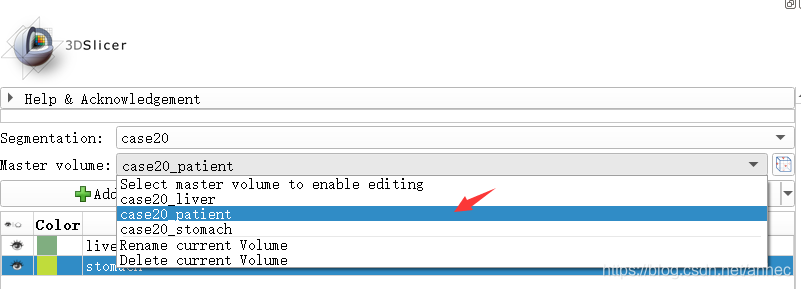

将Master Volume切换为原始体数据: